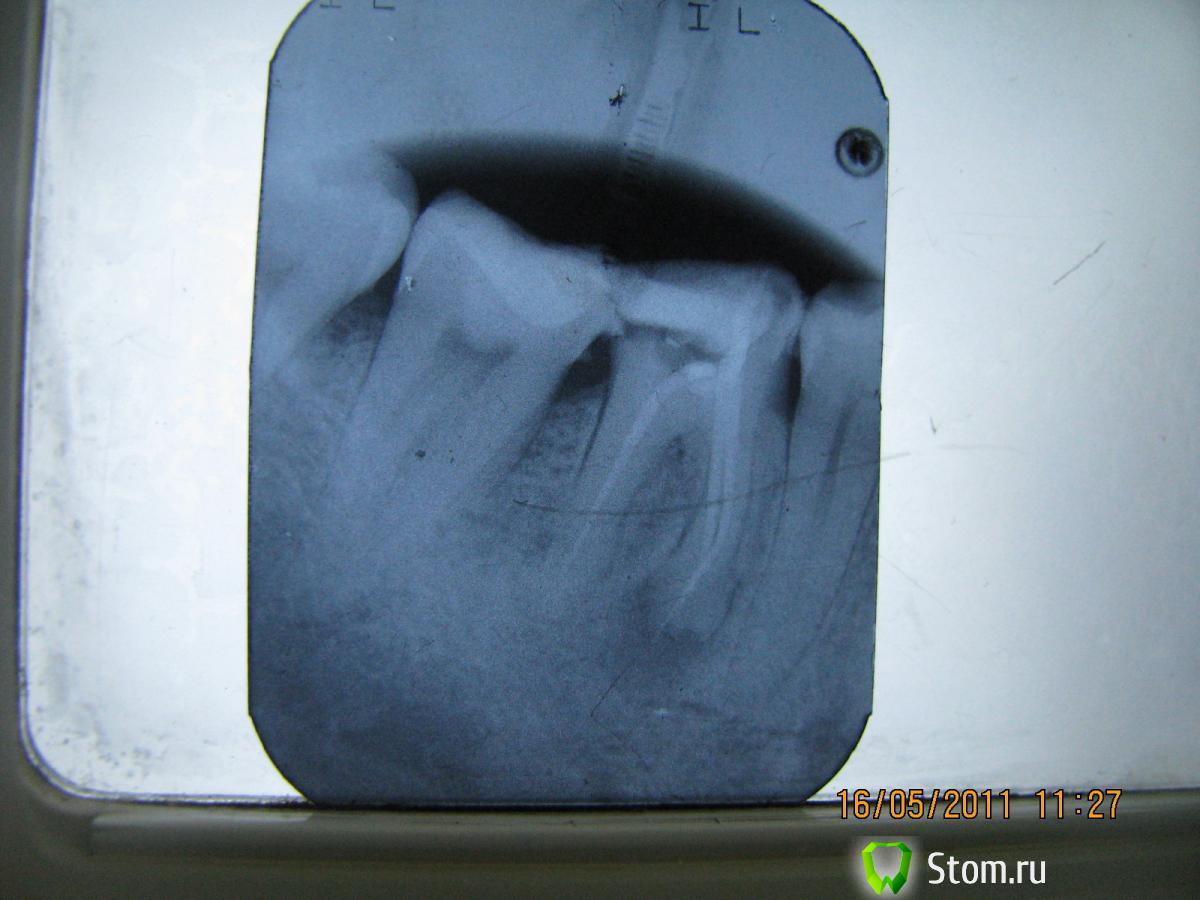

Elenushka Опубликовано 13 января, 2012 Автор Поделиться Опубликовано 13 января, 2012 Вот представляю вашему вниманию пациента.На зубах 45- 47 с 1994 года по 2010г находился металло-керамический мост. НИчего его не беспокоило. Пришел с целью заменить конструкции.(сразу оговорка- он категорически против удаления зубов, денег на эксперименты не жалеет)))Сделала снимок и увидела- перфор, сделанный давным давно,кости как- то маловато. Ну вообщем предлагала удалить, ни в какую. Он мой хороший знакомый, поэтому принялись экспериментировать. 47зуб- был под вкладкой много лет не стали трогать. Вообщем в одно вмешательство- откинут слизисто- надкостничный лоскут, все зачищено, перфор отпрепарирован. Закрыт цементом. Дефект заполнен костью,прикрыт мембраной. Все ушито. следующий снимок сделан совсем недавно( спустя чуть больше 10 месяцев. Запротезирован( мк мост с круговой гирляндой) Снимок работы позже(он в отъезде).В общем на снимочке все так себе вроде бы, а во рту все очень прилично выглядит. Ссылка на комментарий

светляк Опубликовано 15 января, 2012 Поделиться Опубликовано 15 января, 2012 Здравствуйте,коллеги.Не знаю,можно ли назвать экспериментом мой случай или все-таки желание сохранить зуб...: Молодая девушка. Зуб 46-резорциненный-не беспокоил,но коронковая часть разрушена почти полностью(если не учитывать старую ,ужасную пломбу без намека на всякую анатомию).На снимке-резорбция медиальных корней.Конечно,с моей стороны последовало предложение удалить зуб и не рисковать,но пациентка пожелала рискнуть("удалить всегда успею"). И с согласия пациентки со всякими расписками о безгарантийном лечении мы начали лечение,которое продолжалось где-то 4 месяца.Была проведена эндодонтия,заложен каласепт и меняла я кала септ на протяжении лечения 3 или 4 раза.Через 4 месяца,увидев,что разрежение уменьшилось,я запломбировала каналы окончательно.Затем-культевая вкладка и коронка. Вложения-приличные.Но иначе восстановить не получилось бы. Ссылка на комментарий

светляк Опубликовано 15 января, 2012 Поделиться Опубликовано 15 января, 2012 Коллеги,извините,за качество.Ну не очень я дружу с отправкой снимков... Смотреть снимки надо в такой последовательности: 1-5-6-2-3-4. Ссылка на комментарий